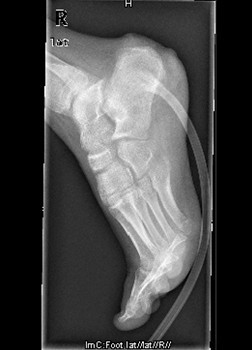

患者男,15岁,因“车祸致右足跟部皮肤撕脱伤清创缝合术后13天”入院。患者13天前因车祸导致右足疼痛流血伴功能障碍,右足跟部皮肤撕脱,遂到当地人民医院就诊,诊断为右跟骨骨折伴跟部皮肤严重剥脱伤,右胫骨远端骨折。急诊下行“右足跟部皮肤严重剥脱伤皮肤严重挫裂伤清创缝合术”。术后给予止痛、消肿、预防感染等对症处理,目前右足外侧及跟部皮肤变暗,坏死。患者为进一步诊疗,故转入我科继续治疗。

查体:右足内踝、外踝及跟部皮肤变暗,部分缺血坏死。未见畸形,稍肿胀。右足趾皮温无明显降低,右足趾感觉未见明显异常。右足内踝、外踝及跟部皮肤局部压痛。右踝关节活动受限,右踝关节活动诱发疼痛。右膝关节活动未见明显异常。 辅查:x片示右跟骨,右胫骨远端骨折。

诊断:1、右足清创缝合术后皮肤软组织坏死伴感染,2、右跟骨骨折,3、右胫骨远端骨折。 治疗:择期手术。